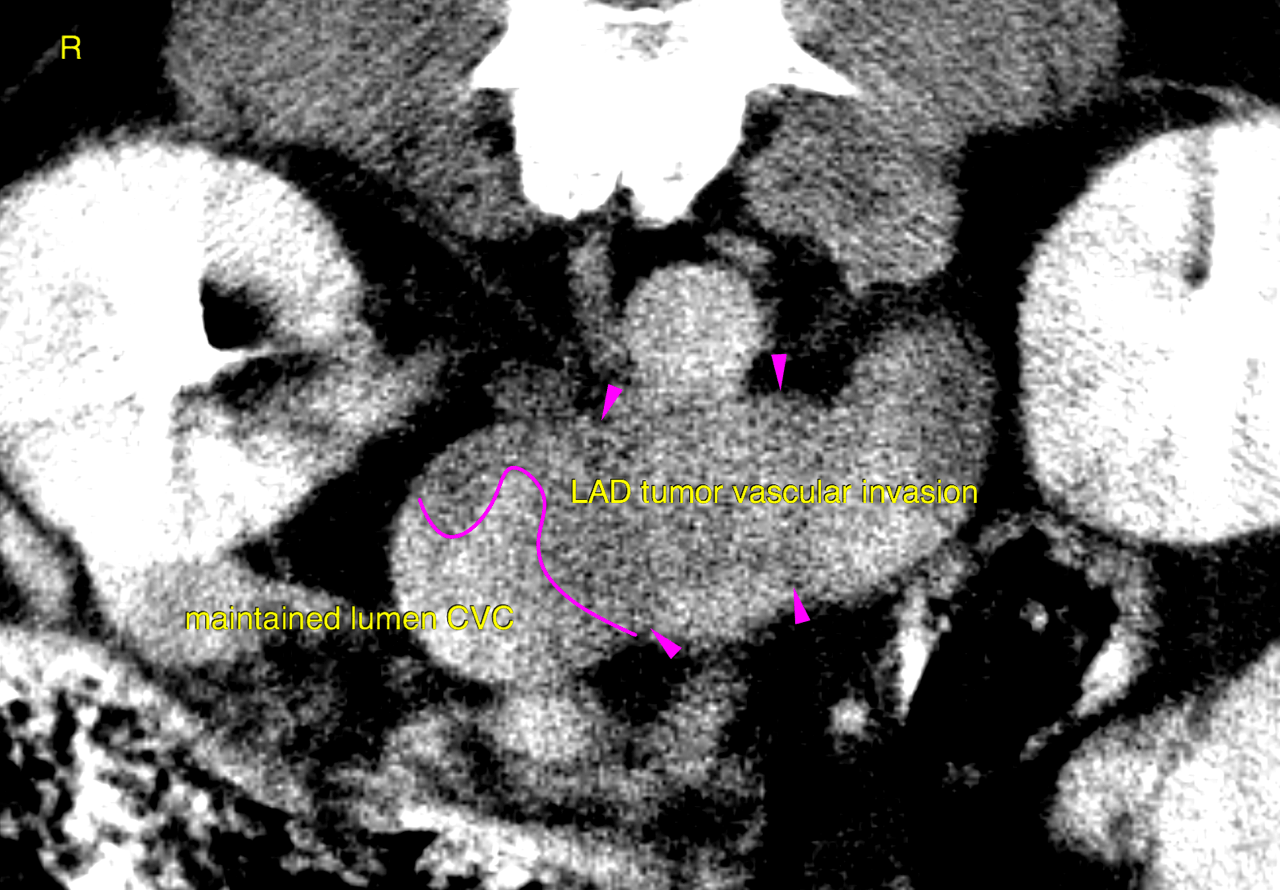

CT of the abdomen – A leftsided polygonal expansile and slightly ill defined adrenal mass of 4 x 3.5 x 4 cm is seen. The mass reveals extensive invasion into the caudal vena cava obstructing 60 % of the vascular diameter and expanding the vascular lumen signifcantly. The intravascular tumor extends at least 7 cm cranial from the right renal vein. Marginal blood flow is maintained. Pooling of contrast caudal to the vascular mass with differential contrast concentration is seen. The mass itself reveals a heterogenous attenuation pattern with non-uniform contrast enhancement. Mild localized retroperitoneal effusion and fat stranding is noted surrounding the mass.

¥ Leftsided adrenal mass with extensive vasular invasion meeting malignancy criteria ¥ Mild paraneoplastic retroperitoneal effusion ¥ Normal right adrenal gland Reactive mesenteric lymph node hyperplasia. The changes do not meet malignancy criteria at this point.